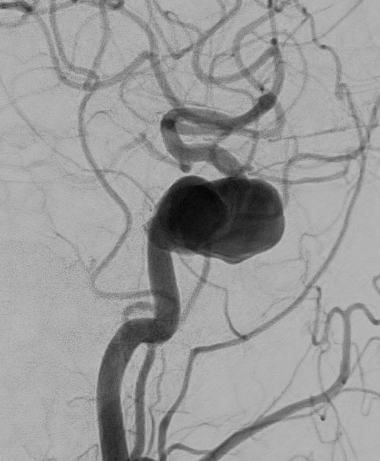

脳動脈瘤

【脳動脈瘤】

クリッピング後

【クリッピング後】

コイル塞栓術後

【コイル塞栓術後】

治療の方法は、開頭して動脈瘤にクリップをかけるクリッピングという方法と、コイル塞栓術といって頭を開けないでカテーテルで治療する方法があります。どちらの手段にも有利な点と不利な点があり、当院では動脈瘤の場所、形状、患者さんの状態などに応じて両者を使い分けています。